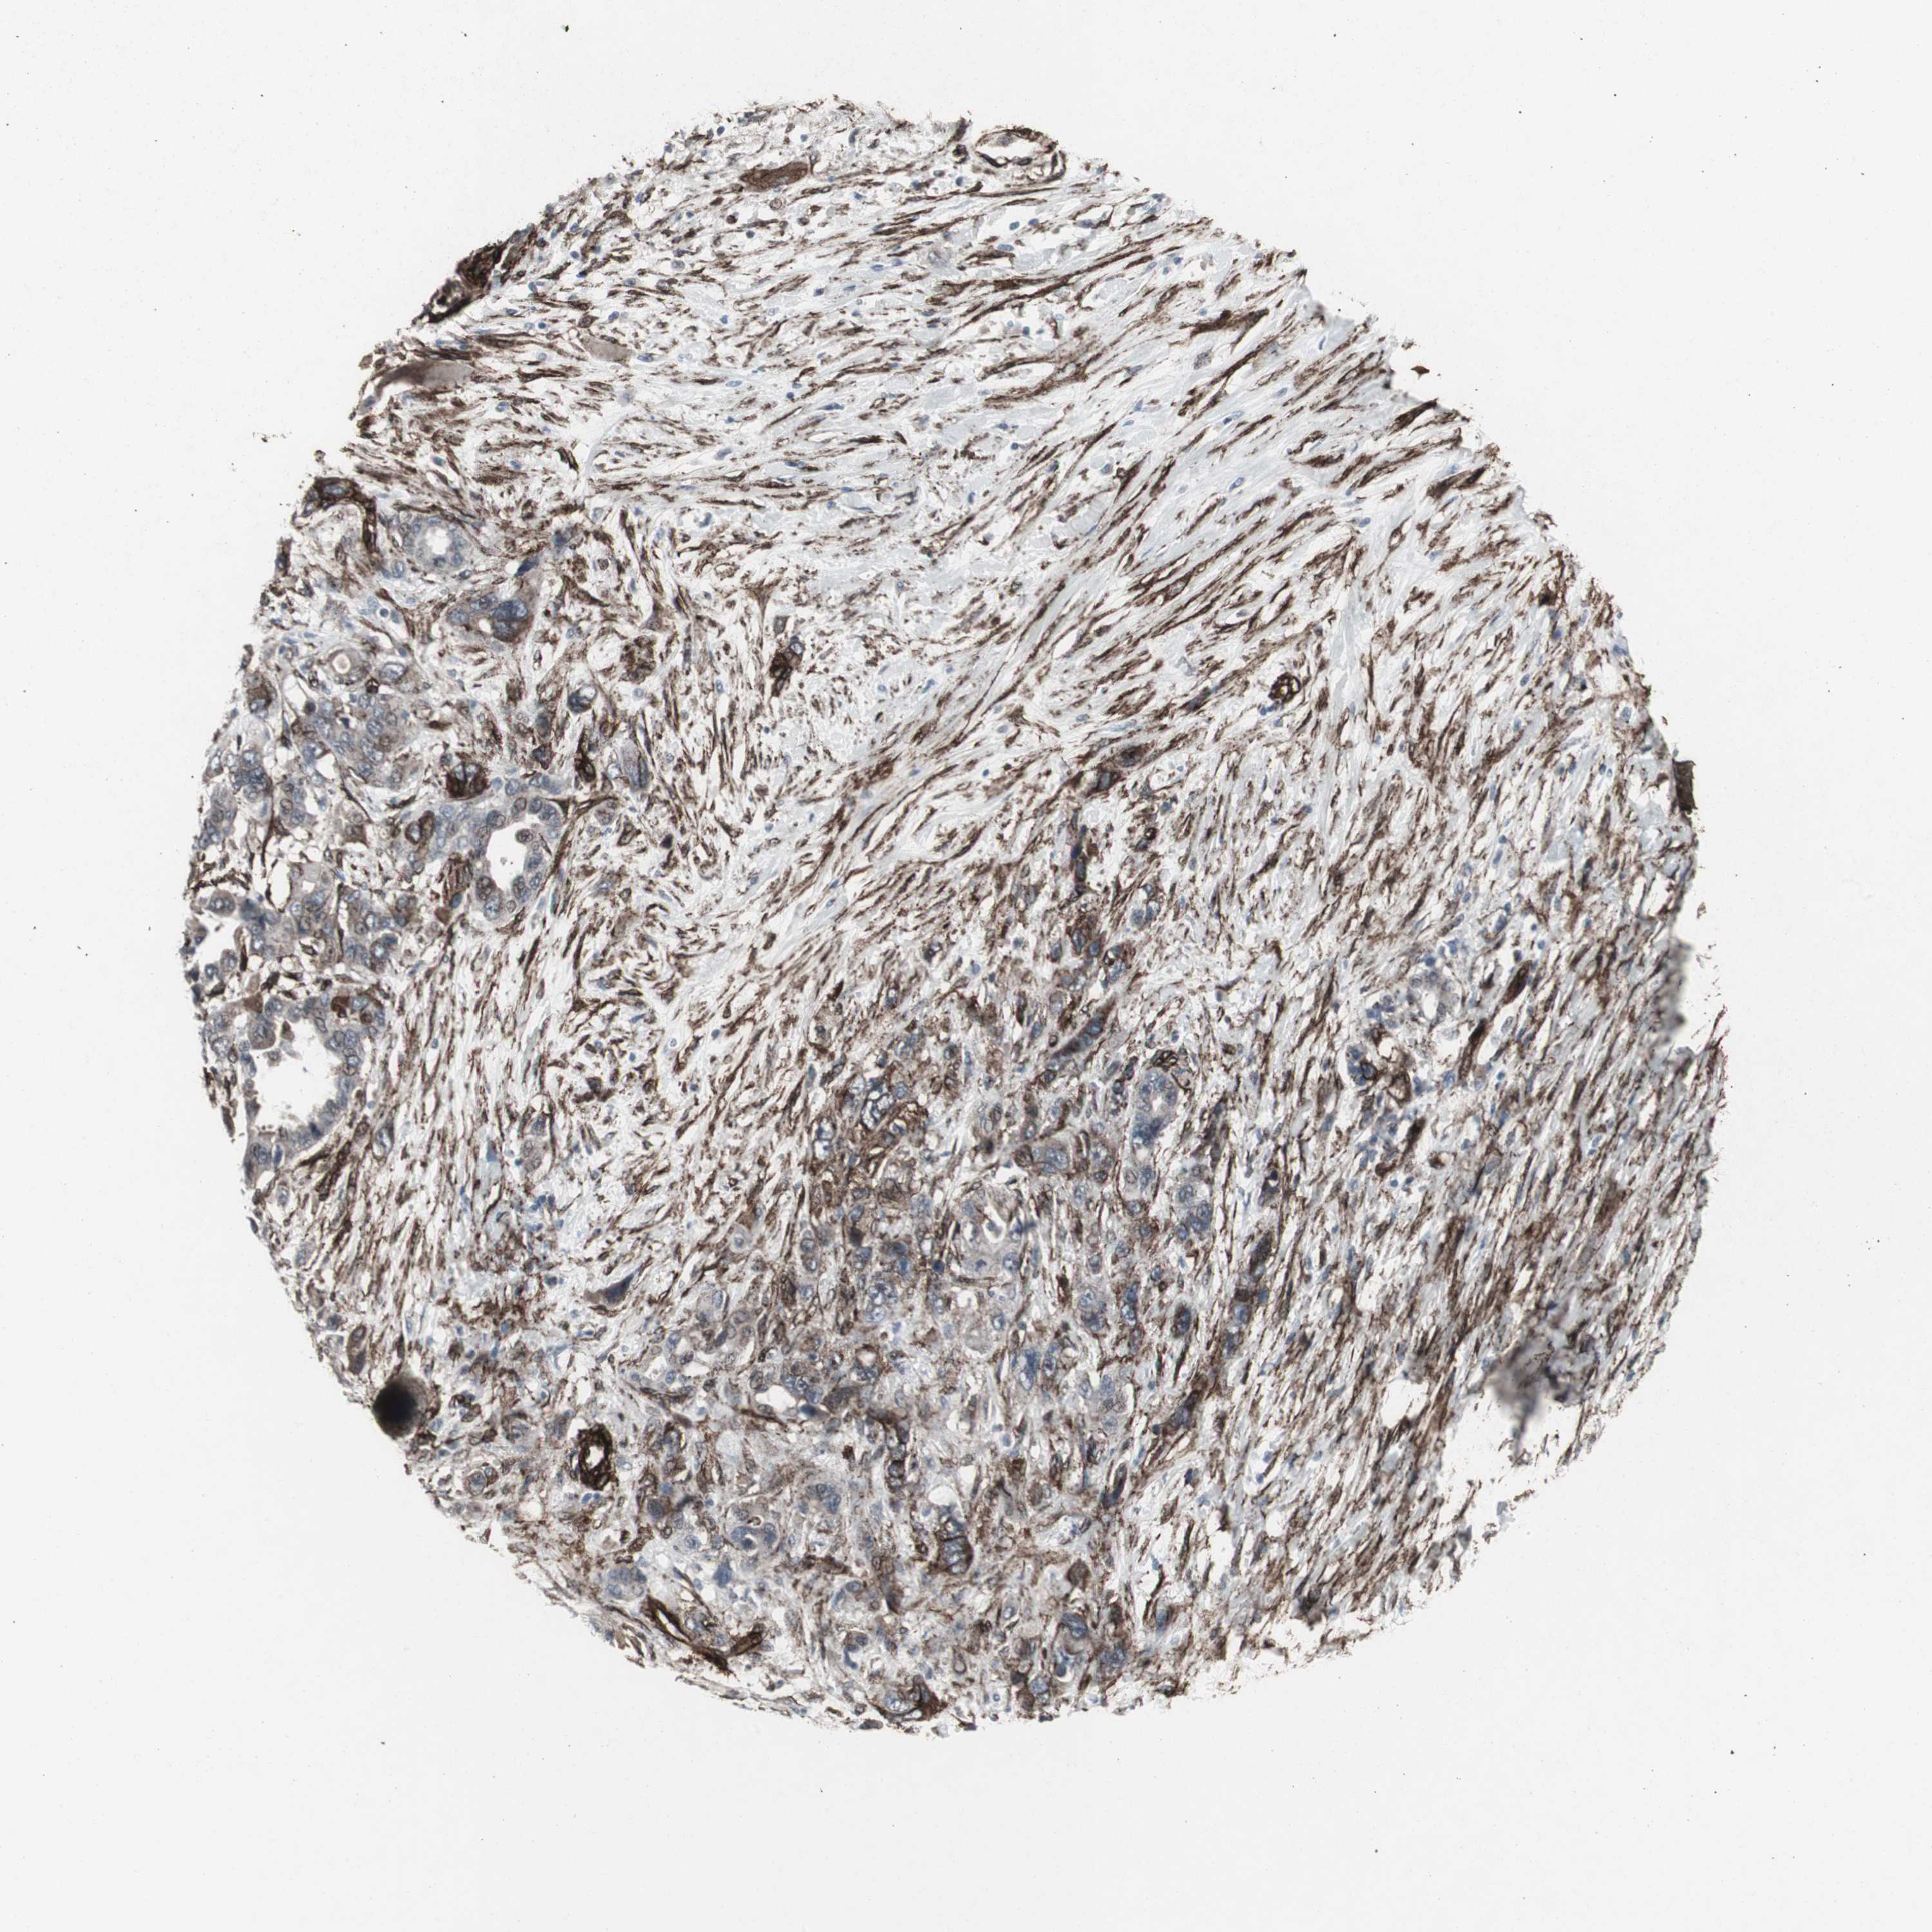

PANCREATIC CANCER - Protein expressioni

A mouse-over function shows sample information and annotation data. Click on an image to view it in a full screen mode. Samples can be filtered based on level of antibody staining by selecting one or several of the following categories: high, medium, low and not detected. The assay and annotation is described here.

Note that samples used for immunohistochemistry by the Human Protein Atlas do not correspond to samples in the TCGA dataset.

Antibody stainingi

Antibody staining in the annotated cell types in the current human tissue is reported as not detected, low, medium, or high, based on conventional immunohistochemistry profiling in selected tissues. This score is based on the combination of the staining intensity and fraction of stained cells.

Each image is clickable and will lead to virtual microscopy that enables deeper exploration of all samples and also displays staining intensity scores, fraction scores and subcellular localization as well as patient and tissue information for each sample.

Antibody CAB005579

Staining

High

Medium

Low

Not detected

Intensity

Strong

Moderate

Weak

Negative

Quantity

>75%

75%-25%

<25%

None

Location

Nuclear

Cytoplasmic/membranous

Cytoplasmic/membranous,nuclear

Adenocarcinoma, NOS

Adenocarcinoma, metastatic, NOS